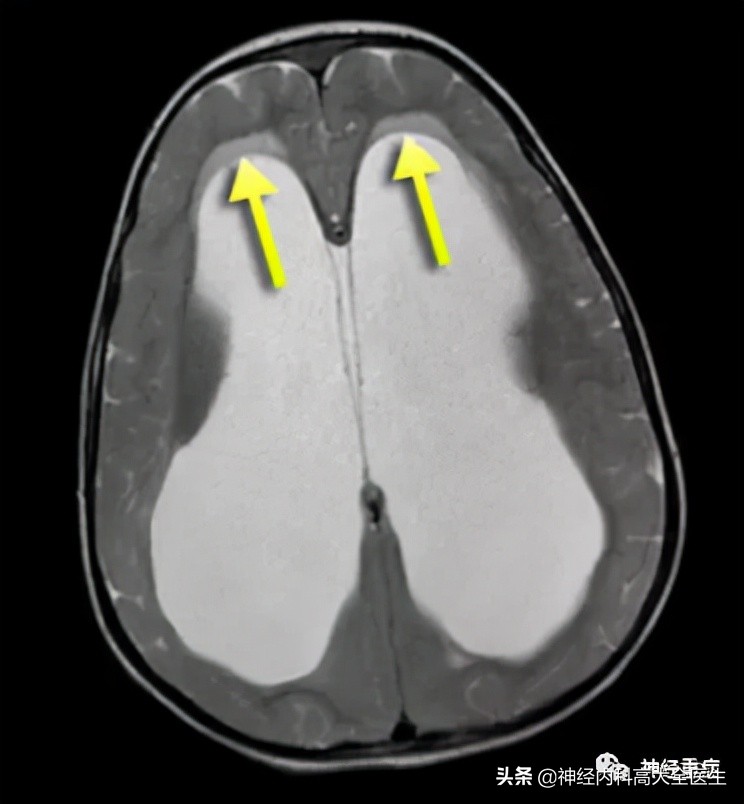

3.间质性脑水肿

常见于梗阻性脑积水。不同病因引起梗阻性脑积水,使脑室系统扩大,尤以侧脑室扩大为甚,致使脑室内压力显著高于脑组织内的压力。产生脑室内-脑组织内压力梯度,这种压力梯度的显著差别,使脑室内液体可以透过脑室室管膜到脑室周围脑组织中,形成脑室周围白质脑水肿。